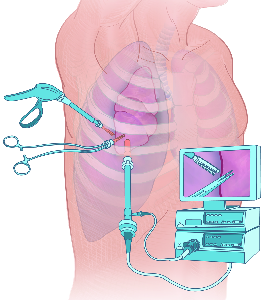

Detailreiche Fotografien aus der medizinischen Praxis ergänzen die Texte; moderne, genaue,

wissenschaftliche Zeichnungen geben Einblick in die Anatomie und die Funktion der Lunge und

anderer Organe.